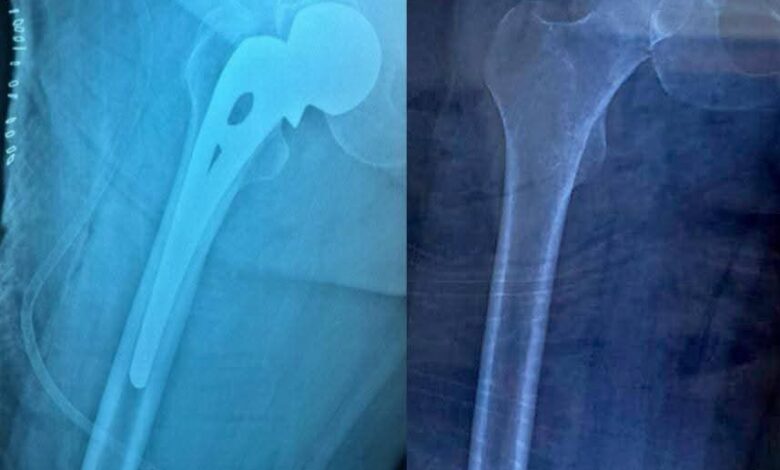

اجراء عملية تبديل مفصل الورك لمريضة بعمر (70) عام تعاني من مرض الزهايمر في مستشفى الكرخ العام

اجرى فريق طبي متخصص بجراحة العظام والكسور برئاسة الدكتور مصطفى حبيب عملية تبديل مفصل الورك لمريضة بعمر (70) عام تعاني من مرض الزهايمر وآلالام شديدة وعدم القدرة على الوقوف أو المشي وأجريت له كافة الفحوصات الطبية اللازمة وادخلت المريضة الى صالة العمليات وتكللت العملية بالنجاح حيث تم تبديل مفصل الورك احادي القطب والمريضة بحالة صحية جيدة .